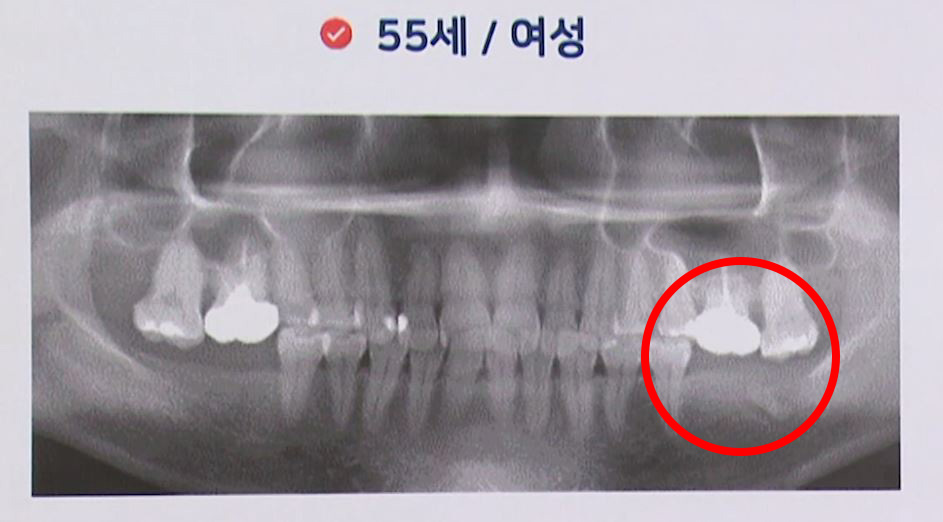

한 분은 아랫니의 공백이 있었고, 앞서 보신 분은요. 지금 보신 분은 위쪽에 이제 치아가 공백이 있습니다.

이분은 치아가 상실된 건 없습니다. 제2 대구치까지 다 있는 경우인데 한꺼번에 빼야 할 치아를 오히려 발치하지 않고 치료를 미루기만 하다 보니까. 우리가 귤 상자에서 귤이 하나 썩어가는데 솎아내지 않고 그냥 있다 보면 그렇죠. 그 곰팡이 균들이 담대로 퍼지듯이, 아까도 말씀드렸지만 각종 많은 박테리아와 세균들. 구강 내에도 곰팡이 균이 있습니다. 푸르스름하게 치석이 끼기도 하거든요. 그래서 이것들이 퍼지는 겁니다, 사실은. 우리가 잘 때는 우리가 그 균에 대항할 수 없잖아요. 그래서 양치도 주무시기 직전에 하는 게 좋고 어쨌든 이런 경우에 치료를 계속 미루다가 발치하게 되면 굉장히 치료 기간이 길어지게 되고.

그다음에 많은 치아를 뺄 수 없기 때문에 꼭 반드시 빼야 할 치아들만 발치하고 기다립니다. 기다리고 나머지 치아에 대해서는 만성 치주염에 대한 전문가적인 치료를 들어가게 되겠죠. 대부분의 경우에 이렇게 치은 소파술이라고 해서 치아의 뿌리 형태에 맞게 되어 있는 기구를 사용하거나 요즘 같은 경우는 임플란트 주위염이나 또 치아 주위염에 또 레이저를 적용해서 치료를 하는 경우도 많은 좋은 결과를 얻고 있습니다. 어쨌거나 할 수 있는 방법을 총동원하고 이쪽에는 이식을 하고 3개월 기다렸다가 수술을 하는 날 바로 임시치아를 하게 되는 방법을 채택했습니다. 그래서 3개월 동안은 골 이식을 한 다음에 임시 틀니를 이렇게 끼었다 뺐다 하는. 틀니를 장착을 한 후에 수술한 그날 지나고 하루 수술하고 나서 중간 지대주를 연결하고 하루 있다가 오신 경우입니다. 그다음에 이제 임플란트 식립하고 하루 뒤에 임시치아를, 그전에는 임시 틀니를 끼다가 임시치아를 바로 장착한 경우입니다. 이걸 하고 나서 이제 3개월 지났지만 계속해서 남아 있는 다른 어금니 부위에 치주 관리나 후속 처치가 필요한 경우라고 볼 수 있습니다.